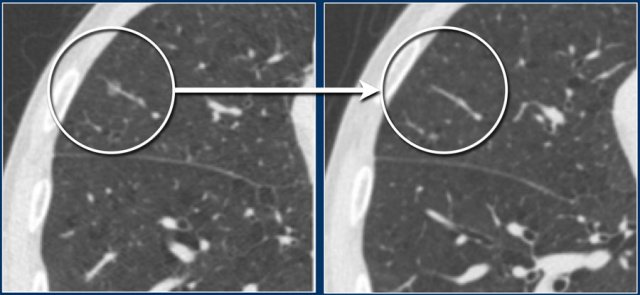

Persistent malignant subsolid nodule Persistent malignant subsolid nodule

These images show a pure groundglass subsolid nodule in the right lower lobe.

This lesion demonstrated growth in a two year interval and proved to be malignant after resection.